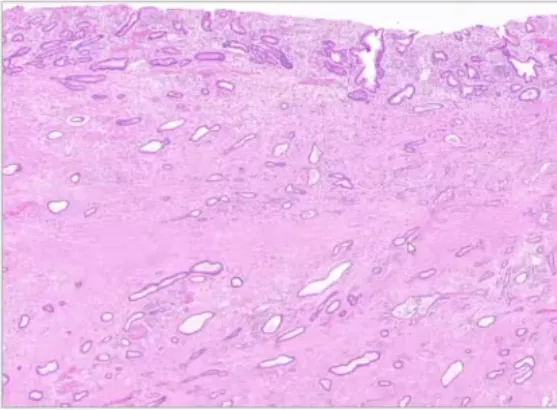

胆管导管内管状乳头状肿瘤 新增

(ITPN, Intraductal tubulopapillary neoplasm of the bile ducts)

• 定义:是一种非侵袭性、管腔内生长的上皮性肿瘤,无明显黏液产生,主要由高级别异型增生的上皮细胞形成管状/少量乳头状结构;

• 病理:大体为实性结节充填扩张胆管,无明显黏液;镜下呈筛状管状结构,高级别异型增生,少见黏液,坏死常见;免疫组化CK7 CK19+,80% MUC1+,30-100%MUC6+,MUC2, MUC5AC -;

• 进展:约80%进展为浸润癌,多为普通型胆管癌;

• 预后:切除后预后极好,5年生存率约90%;伴浸润癌者5年生存率约75%,优于普通胆管癌。